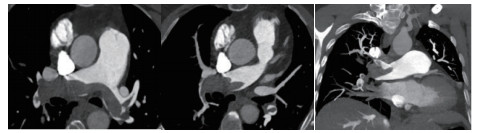

例4 62岁,女性,主诉“活动后气短20 d,加重1 d伴晕厥1次”。患者入院20 d前上近20级台阶后感气促,休息后缓解,未重视。入院前1 d,突发晕厥伴有轻微活动后明显的呼吸困难。既往:左下肢静脉曲张病史3~4年;入院40 d前患者左足跖骨骨折,接受外固定,尚未影响日常活动,未接受抗凝治疗;发现血小板减少数年(血小板维持5.5~8.6 g/L,末次于一年前血小板85 G/L),未明确原因及治疗;血气分析提示pH 7.447,PaCO2 32.2 mmHg,PaO2 85.3 mmHg,SaO2 96.8%;D-Dimer 1 947 ng/mL;FDP 22.84 μg/mL,FBG 2.05 g/L;PLT 51G/L;cTnI 0.52 ng/mL,BNP 299 pg/mL;ALT 318 U/L,AST 300 U/L,CREA 74.8 μmol/L,血Na+、K+、Cl-:正常范围;UCG提示:右心大,肺动脉主干轻度增宽(28 mm),三尖瓣反流(重度),反流面积13.7 cm2,TI法估计SPAP为30 mmHg、左室舒末内径35 mm、左室舒张功能受限(E/A 1:1.5)、未见节段性室壁运动障碍;双下肢静脉超声提示左侧腘静脉不完全血栓。心电图(图 12所示)提示窦性心动过速、SⅠQⅢTⅢ;CTPA显示肺动脉分叉处及双肺亚段充盈缺损(图 13所示)。

| 图 13 入院时CTPA结果显示肺动脉分叉处及双肺亚段充盈缺损 |

入院查体:神志清楚,体温36.5℃,血压120/70 mmHg,脉率110次/min,呼吸22~26次/min,指氧饱和度93%(安静,空气氧),未见乏氧征。双肺呼吸音清,未闻及干湿性啰音,心率110次/min,律齐,P2 > A2,心界无扩大,无杂音,腹软,无压痛,肠鸣音正常。神经系统未见异常。左下肢膝关节以下可见静脉曲张,双下肢无浮肿。入院诊断:急性肺血栓栓塞症(中高危);左下肢静脉曲张并血栓形成;血小板减少症;肝功能不全。处理方法及原因:患者中年,日常生活质量高;入院20 d前虽有症状,但入院1 d前明显加重并出现晕厥发作;两次D-Dimer检查均<2 000 ng/mL,与CTPA显示的血栓负荷不匹配。入院后连续两次检测血小板均低于正常(51~77 g/L)。因考虑病史较长但近期有加重、血小板低等原因系统溶栓治疗出血风险较大,所以给予导管介入碎栓并行肺动脉内溶栓治疗(r-tPA 20 mg)。溶栓2 h后患者症状明显缓解,复查D-Dimer 12 560 ng/mL,序贯肝素抗凝并复查CTPA提示原有血栓明显消失(图 14所示)。